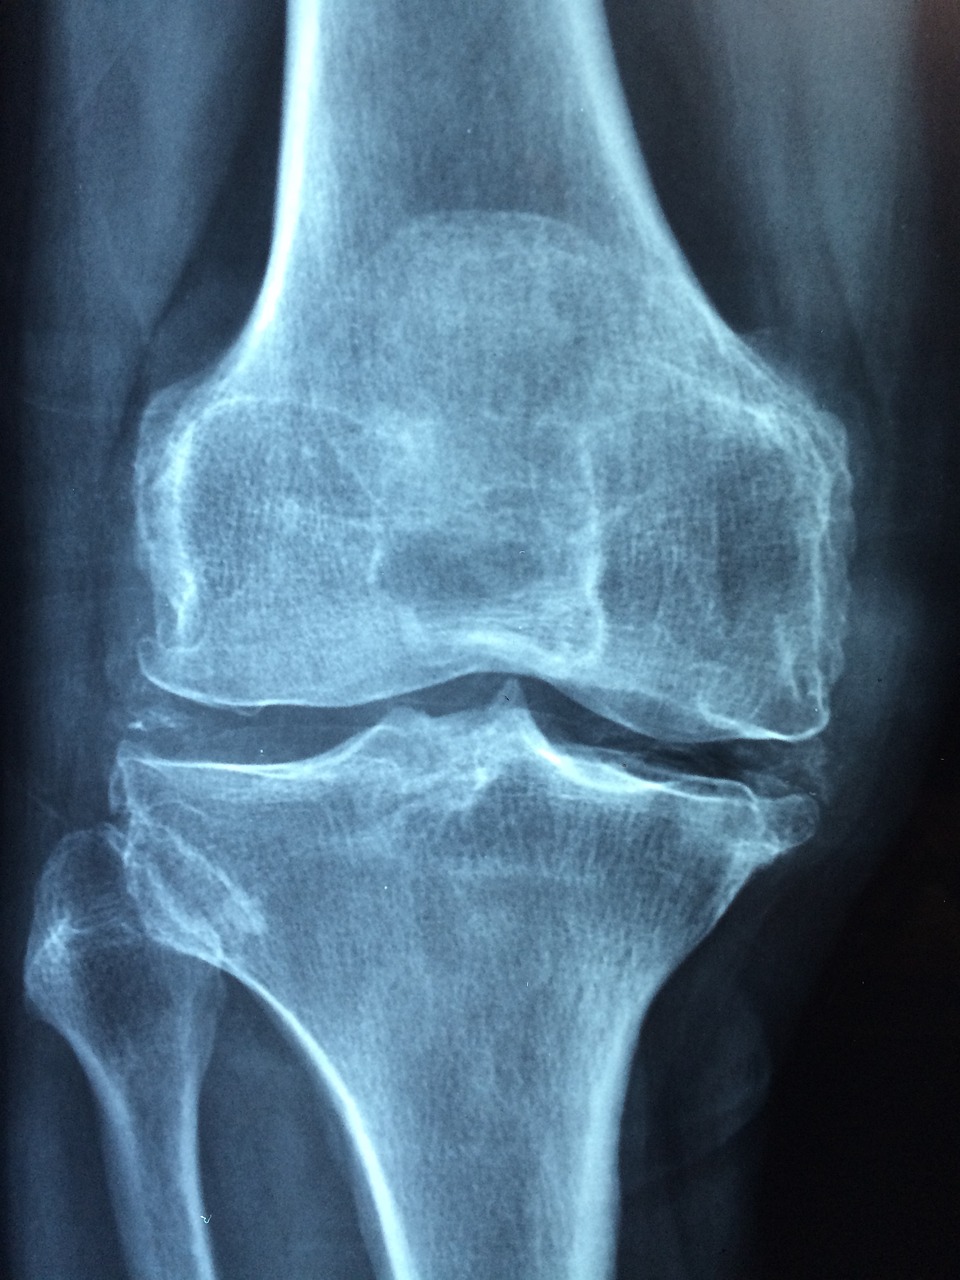

골다공증은 골밀도와 강도가 감소되어 손상의 위험이 증가하는 특징이 있습니다. 그 결과 골절의 위험이 증가하고, 작은 충격에도 큰 손상이 발생할 수 있습니다. 골다공증의 가장 흔한 원인 중 하나는 호르몬 수치의 변화입니다. 특히 폐경 후 에스트로겐 수치의 급격한 감소는 골밀도 감소와 직접적인 관련이 있습니다. 에스트로겐은 뼈를 튼튼하게 유지하는 데 중요한 역할을 하기 때문에 골밀도의 감소로 이어질 수 있습니다. 남성의 경우 테스토스테론 수치가 나이가 들면서 점차 감소하는데, 이는 골밀도에도 영향을 미칠 수 있습니다. 적절한 영양소의 섭취는 뼈 건강을 유지하기 위해 필수적입니다. 특히 칼슘과 비타민 D는 골다공증을 예방하는 데 매우 중요한 역할을 합니다. 칼슘은 뼈의 주성분이며, 비타민 D는 칼슘의 흡수를 돕습니다. 하지만, 많은 사람들은 이러한 중요한 영양소를 충분히 섭취하지 못합니다. 특히, 노인이나 특정 질환을 가진 사람들은 칼슘과 비타민 D가 부족하여 골밀도가 감소할 위험이 높습니다. 흡연과 과도한 알코올 섭취는 골다공증의 위험을 증가시킬 수 있습니다. 이러한 습관은 뼈 건강을 해치고 여러 가지로 작용하여 골밀도를 감소시킵니다. 또한, 활동성이 낮은 생활습관은 골다공증의 위험인자입니다. 규칙적인 운동은 뼈를 튼튼하게 하고 골밀도를 증가시키기 때문에 활동적인 생활이 중요합니다. 마지막으로, 일부 약물의 장기간 사용은 골밀도에도 부정적인 영향을 미칠 수 있습니다. 골다공증은 다양한 내외부적 요인에 의해 발생하는 복잡한 질병입니다. 질병을 이해하고 예방하기 위해서는 호르몬의 변화, 영양소의 부족, 생활습관과 환경적 요인이 골밀도에 어떤 영향을 미치는지에 대한 깊은 이해가 필요합니다.

골다공증의 가장 직접적이고 흔한 합병증은 골절입니다. 특히 척추의 고관절 골절, 손목 골절은 골다공증 환자들 사이에서 자주 보고되는 부위입니다. 고관절 골절은 회복이 어렵고 장기간의 재활이 필요하며, 때로는 골다공증 환자의 사망률 증가의 주요 원인 중 하나로 여겨집니다. 척추 골절은 환자의 자세와 키에 영향을 미치며, 심한 통증과 함께 일상생활을 크게 방해합니다. 손목 골절 역시 일상활동에 큰 제약을 주며, 특히 노인의 경우 회복이 느리고 어려울 수 있습니다. 골다공증이 악화되면 골절 외에도 만성적인 통증을 겪는 경우가 많습니다. 이러한 통증은 환자의 삶의 질을 현저히 떨어뜨려 때로는 우울증, 불안 등 정신적인 문제로 이어지기도 합니다. 또한 골다공증으로 인한 골절이나 변형은 신체 기능의 저하로 이어질 수 있습니다. 예를 들어 척추 골절은 신체의 중심을 유지하는데 필수적인 척추의 기능을 저하시켜 걷기, 서 있기 등의 기본적인 신체활동을 어렵게 할 수 있습니다. 골다공증과 관련된 합병증은 환자 개인은 물론 가족과 사회에 큰 부담을 줄 수 있습니다. 골절이나 다른 합병증으로 인한 장기간의 치료와 재활은 상당한 경제적 부담을 수반하며 환자의 가족에게 심리적, 경제적인 영향을 미칩니다. 또한 골다공증 환자의 일상생활에서 독립적인 활동에 대한 제한은 가족 중 한 명이 일을 그만두거나 많은 시간을 환자를 돌봐야 하는 상황으로 이어질 수 있습니다. 이는 가족의 삶의 질을 떨어뜨리고 경제적인 부담을 줄 수 있습니다. 골다공증으로 인한 사회적, 경제적 부담은 국가적 차원에서도 중요하게 고려해야 할 문제 중 하나입니다. 골다공증의 예방과 조기 발견은 이러한 합병증을 최소화하고 환자의 삶의 질을 유지하는데 매우 중요합니다. 적절한 영양섭취와 규칙적인 운동, 생활습관 개선이 골다공증 예방에 도움이 될 수 있습니다. 또한 중년 이후의 남녀는 정기적인 건강검진을 통해 골밀도를 확인하고 필요시 치료를 시작하는 것이 좋습니다.